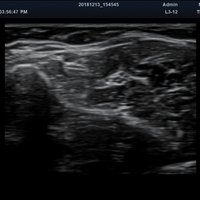

Anwendungsbereiche Abdomen MSK, Nerven, Karotis, periphere Gefäße, Schilddrüse, Mamma

Bildgebungs-Modi B-Modus, CF, M, PW, PD B-Modus, CF, M, PW, PD

• B-Modus: Darstellung zweidimensionale Bilder anatomischer Strukturen